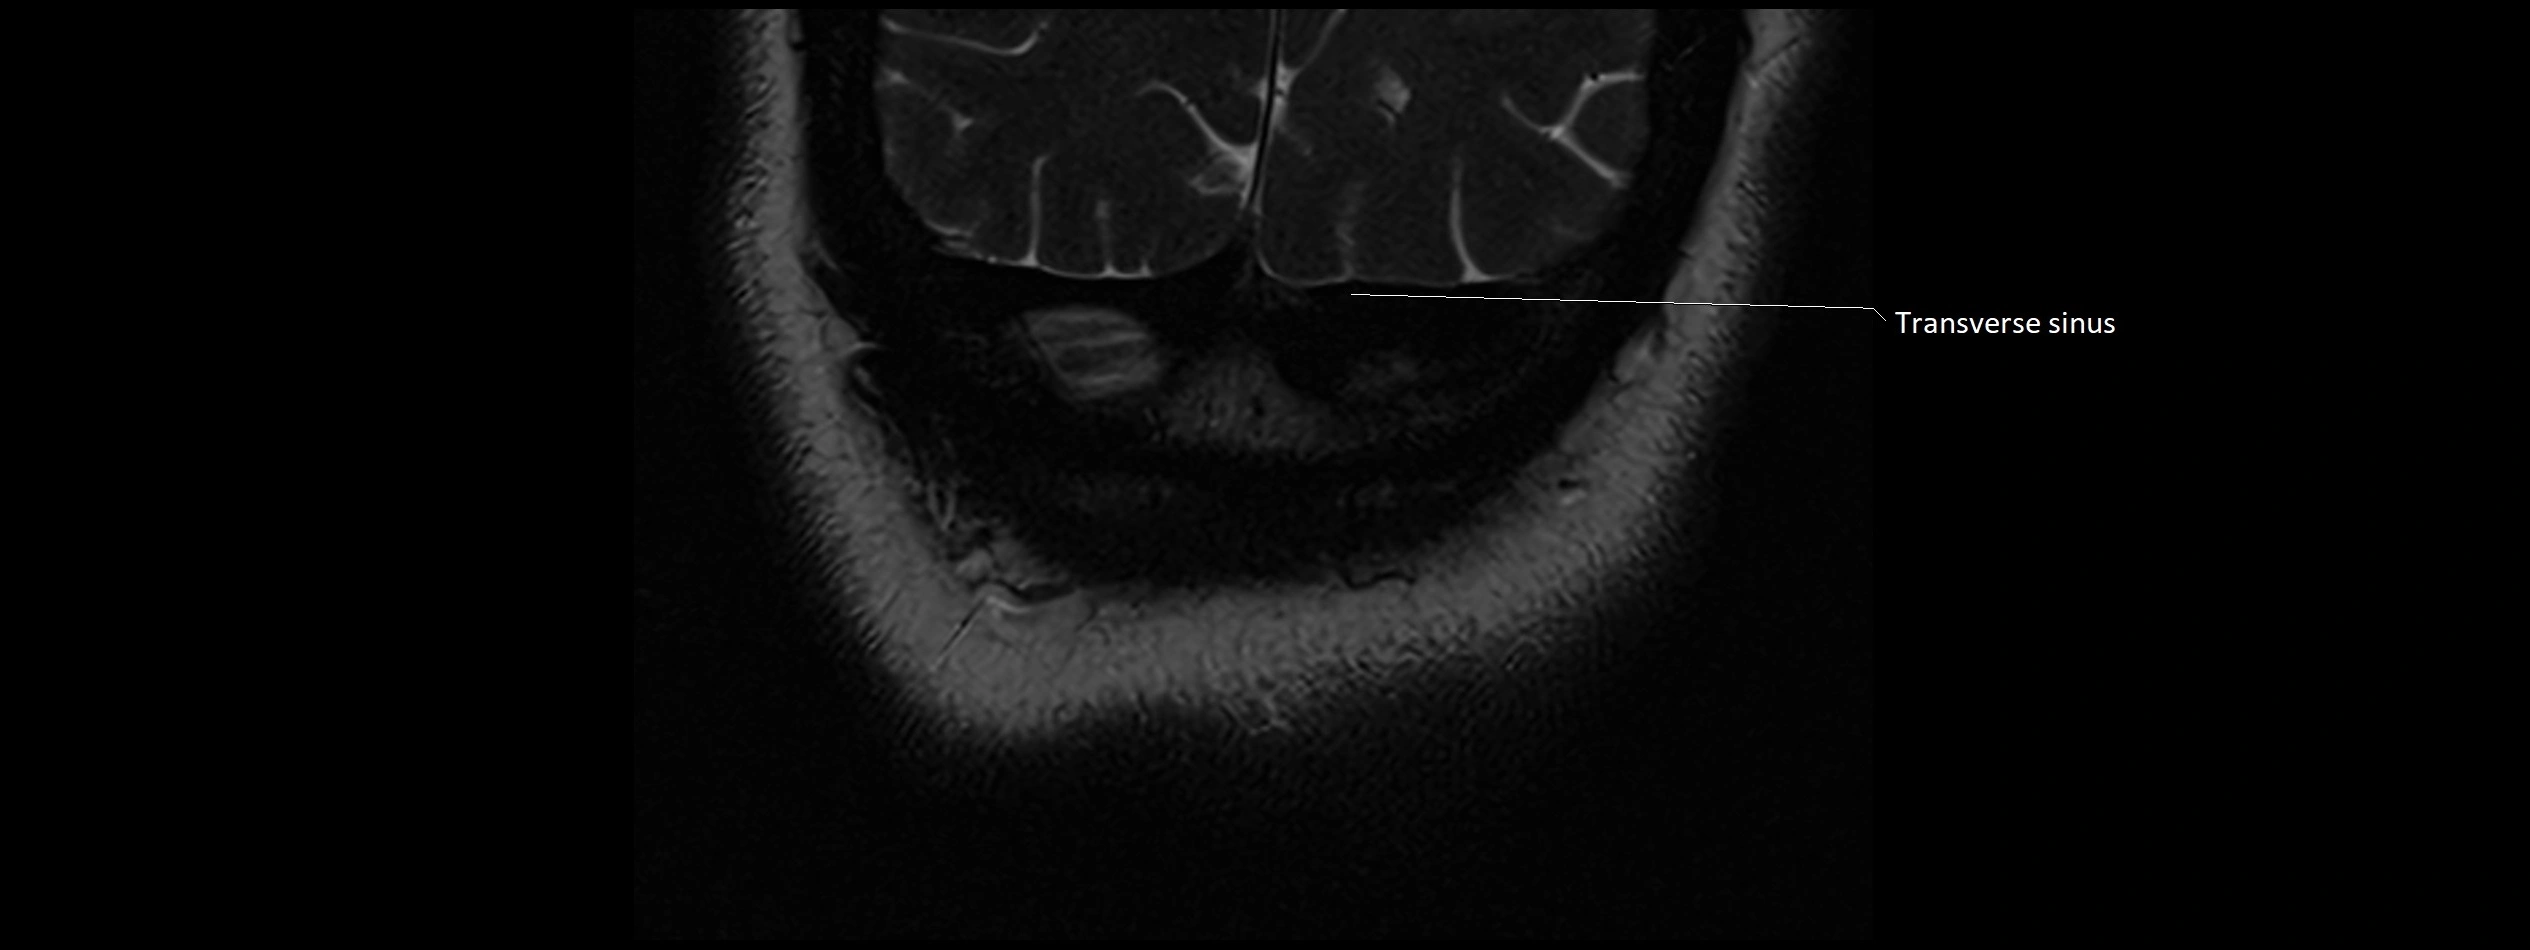

MRI images